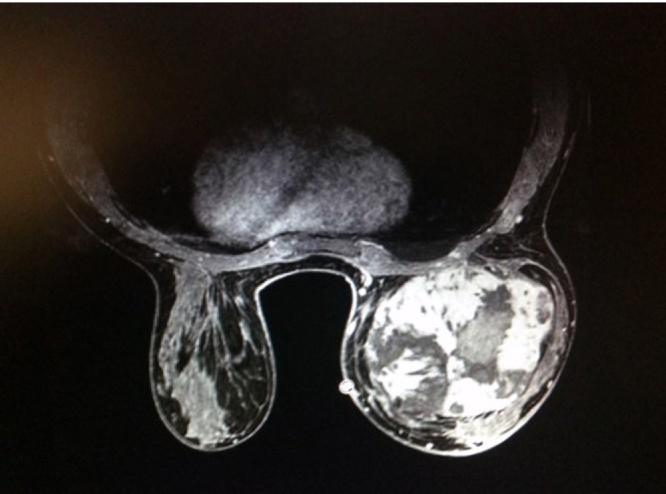

We report a case of primary angiosarcoma of the breast in a 25 years woman, with no previous radiotherapy, treated with a total mastectomy followed by radio-chemotherapy.

我们报告一例25岁女性原发性乳腺血管肉瘤病例,该患者既往未接受过放疗,接受了全乳切除术,随后进行放化疗。